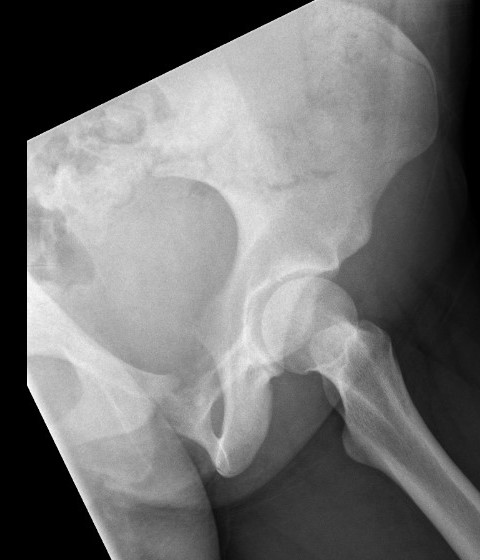

Xray

Often diaphyseal

- diffuse permeative destruction

- can be subtle

Periosteal reaction

- Codman's triangle / onion skinning / sunburst appearance

Ewing's acomion Ewings lesser trochanter

Ewings superior pubic rami